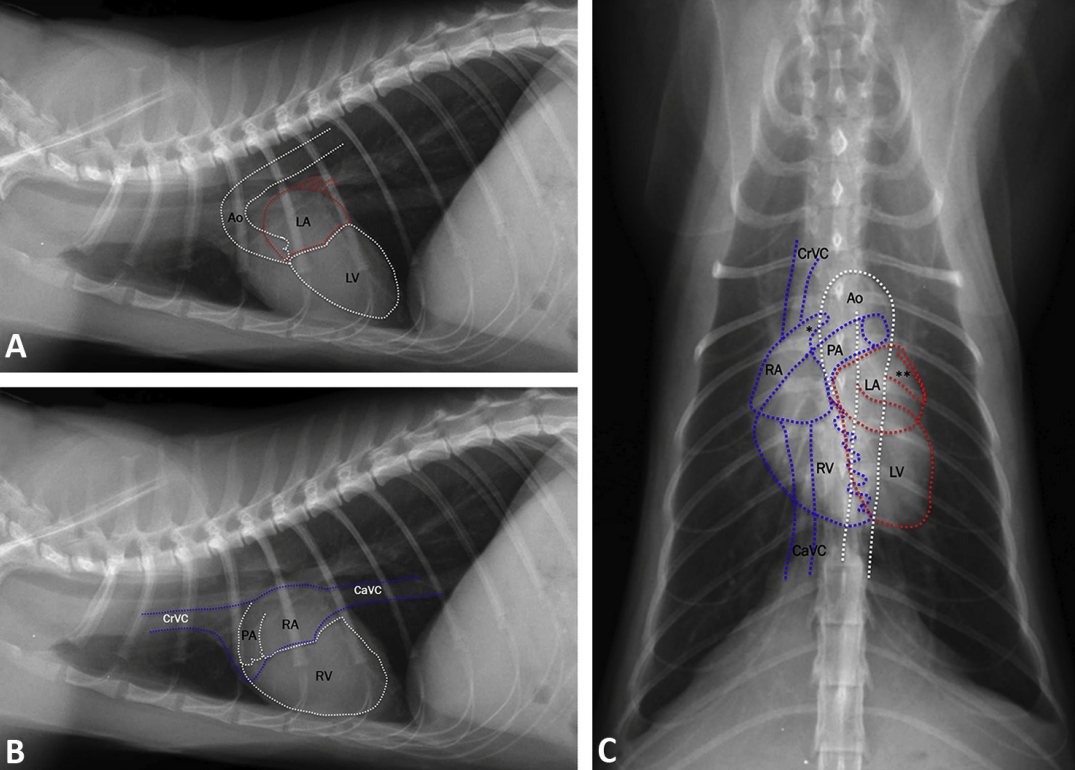

canine and feline VHS : 개와 고양이의 심장 크기평가